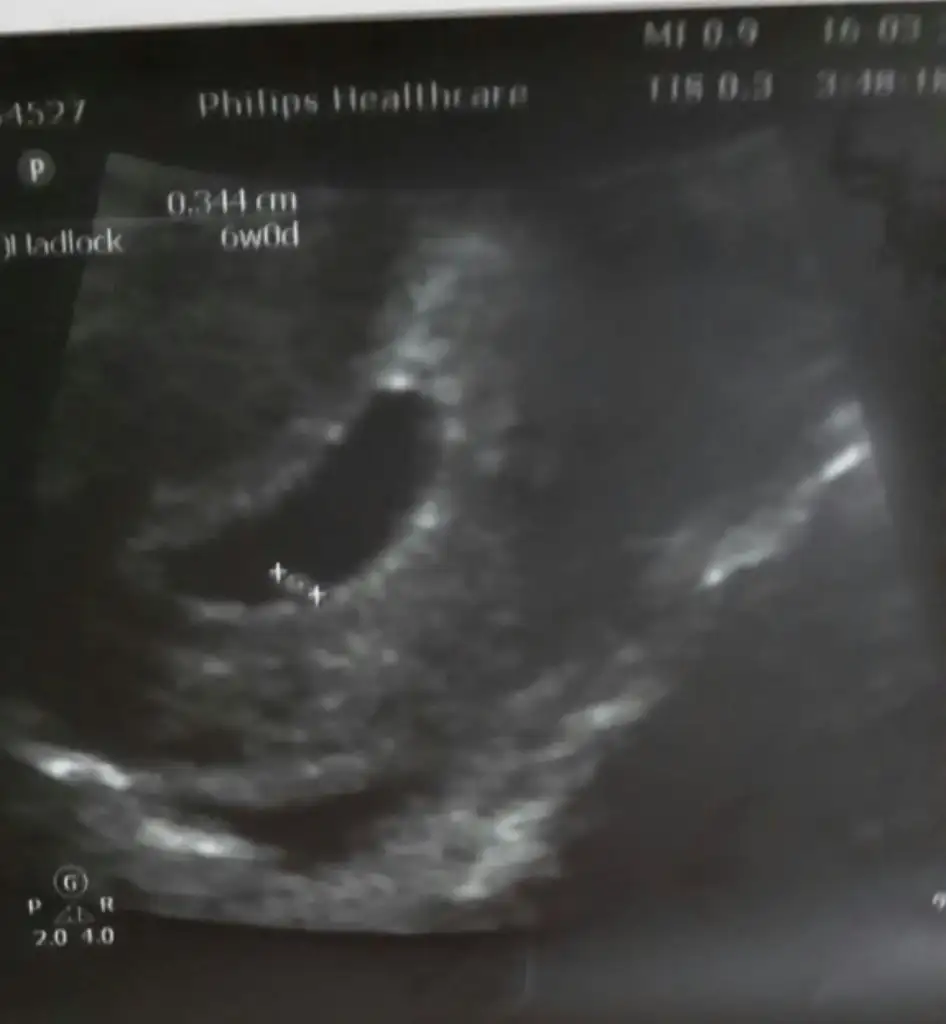

Kızlr bende demin dktr. geldim 8 hfta 3 günlük ultrason kağıdını elime aldığım da sola yakın duruyo kesenin içinde ne trafta olduğunu anlayamadım açıkçası

Sol taraftaKizlarrr bize bakarmisinzzz 7 haftalik usg ama bana ortada gibi geliyor

Cnm benim karin ultrosonunda hep solda gozukuyor sence nedemek biraz acarmisin cnmCanım geçmiş sayfalarda vajinal ise ters hesaplıyormuşsun diye okudum. Mesela karından ultrasonda bebek solda duruyorsa karnında sağda duruyo demek o zaman erkek. Ama vajinalda solda duruyorsa karnında da solda demek o zaman kız. Ama ben bunlara inanmıyorum Kiminde tutuyo kiminde tutmuyo. Onu ancak Allah bilir. Istersen geçmiş sayfalara dön epey bi denk gelirsin demek istediğime. Konunun ilk müdavimleri arasında geçmiş birkaç yıl önce bu vajinal ultrason mevzusu.